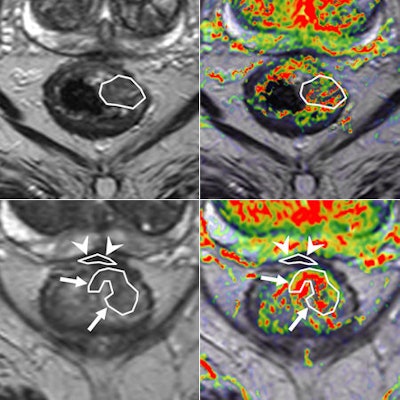

Perfusion MRI of a rectal tumor compared with histology. Top left: T2-weighted MR image of a patient with rectal tumor (encircled) before chemoradiotherapy. Top right: Corresponding perfusion MR image (K-trans map). There is a heterogeneity in tumor angiogenic activity with areas of higher (red) and lower K-trans values. Bottom left: T2-weighted MR image of the same patient after irradiation of the tumor. Bottom right: Corresponding perfusion MR image (K-trans map). Residual tumor (white arrows) is visualized, showing persistent heterogeneous angiogenic activity with areas of high (red) and low K-trans values (arrowheads pointing at fibrosis in the anterior rectal wall). All images courtesy of Dr. Regina Beets-Tan, PhD.However, she emphasized that before these biomarkers can be used in imaging practice, validation of the techniques is required to confirm whether "what you see is also what you get." Ultimately, in the multicenter setting, protocol standardization and implementation are needed to enable large patient cohort validation.